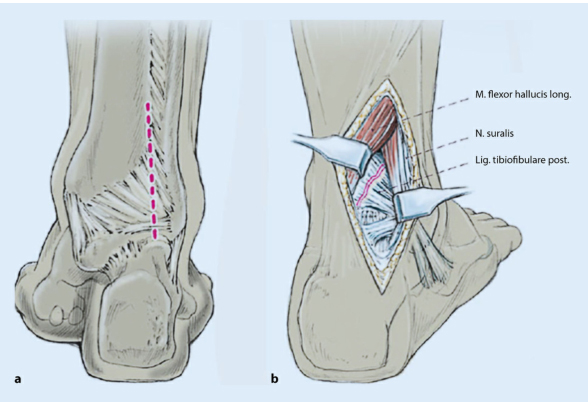

1). С биомеханической точки зрения, имплантация заднелатеральной пластины малоберцовой кости и пластины заднелатеральной лодыжки посредством заднелатерального доступа может обеспечить более стабильную фиксацию при трехлодыжечных переломах.

2). Преимуществом заднелатерального доступа является хороший охват мягких тканей имплантата. (Следующий рисунок).

3). Заднелатеральная пластина малоберцовой кости позволяет фиксировать более длинные винты к дистальному бикортикальному каналу, не проникая в сустав, тем самым обеспечивая большую стабильность. Стягивающие винты также можно имплантировать поперек линии перелома для повышения стабильности.

Техника фиксации пластин. Пластина сначала фиксируется к проксимальному сегменту малоберцовой кости (а), а затем ввинчивается стягивающий винт в качестве инструмента дистальной редукции (б). ПРИМЕЧАНИЕ. Убедитесь, что пластина не достигает верха малоберцовой кости, чтобы не раздражать малоберцовое сухожилие.

разрез кожи